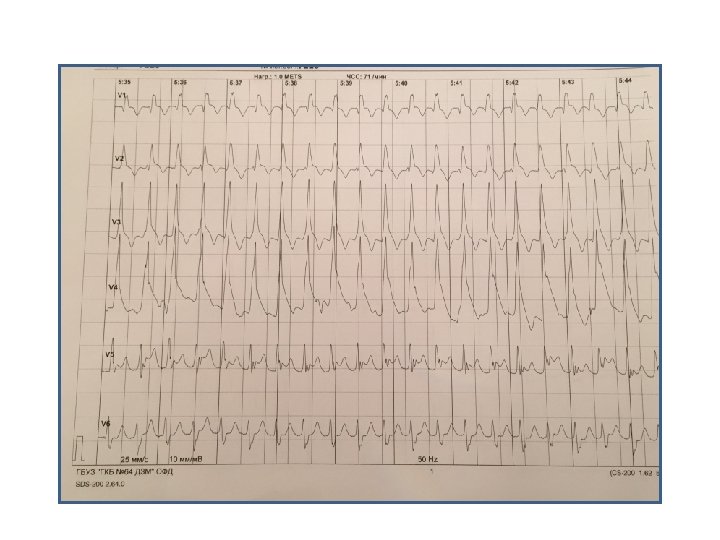

Пациент Б. , 58 лет Направление: диагностика ИБС

Пациент Б. , 58 лет Направление: диагностика ИБС